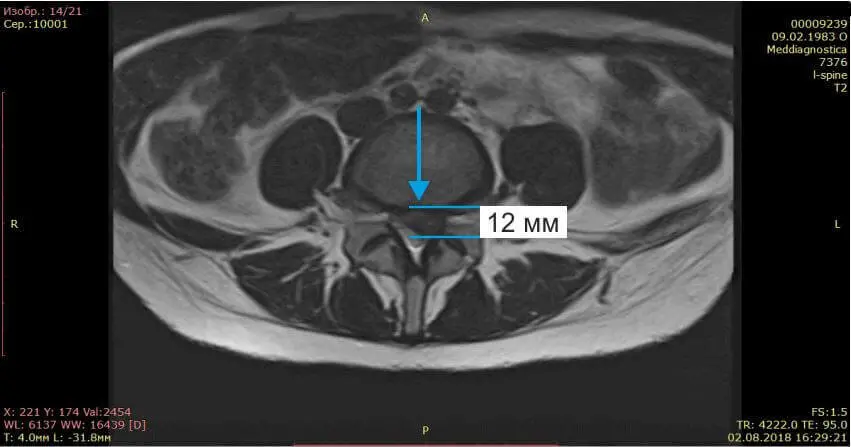

Осмотрели Ирину неврологически и ортопедически, исследовали позвоночник на МРТ и рентгене. Оказалось, что у нее очень большая левосторонняя грыжа размером 12 мм.

Спасибо центру «Меддиагностика» за оказанную помощь. Боли в спине меня беспокоили уже давно, однако я особо не придавала этому значения, обходилась то мазями, то массажами, которые приносили облегчение лишь на время. Забила тревогу я только тогда, когда боли начали отдавать в ногу и пошло онемение ноги.Я сразу сделала МРТ, на котором обнаружилась межпозвоночная грыжа 12 мм, которая сдавливала седалищный нерв. Пропила таблетки противовоспалительные, витамины, но облегчения особого не было, боль в спине уменьшилась, но нога продолжала неметь.Ходили на консультацию к нейрохирургу, но там ответ один — оперативное лечение. Операцию я делать побоялась, решила испробовать другие методы. Друзья мне посоветовали обратиться в центр «Меддиагностика». Мне здесь назначили курс лечения позвоночника и сказали, что с операцией спешить не стоит, прооперировать всегда можно успеть. Я прошла сухую вытяжку позвоночника, курс массажей, уколы вдоль позвоночника. Ногу стало постепенно отпускать и на 6-7 сеанс прошло онемение пальцев.После лечения назначили лечебную физкультуру для закрепления эффекта. В итоге моя грыжа с 12 мм уменьшилась до 2мм! Я очень рада, что попала в этот центр, где работают профессионалы своего дела, которые ставят людей на ноги и оказывают реальную помощь. Отдельно большое спасибо профессору Гонгальскому Владимиру Владимировичу. Это человек с большой буквы и профессионал своего дела!!! Рекомендую всем этот центр. Спасибо Вам большое, что Вы есть! С уважением, Ремига Ирина